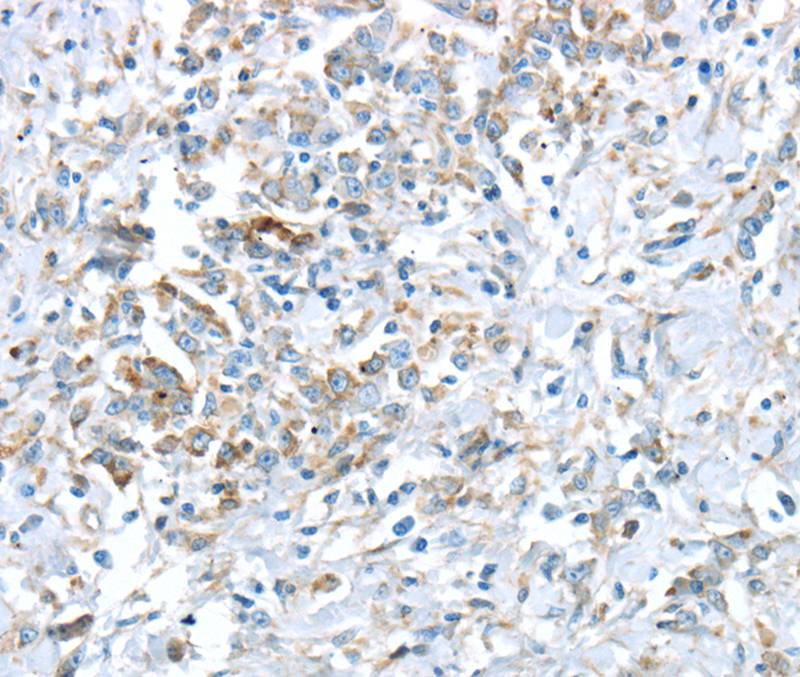

Immunohistochemical analysis of paraffin-embedded Human gastric cancer tissue using #40403 at dilution 1/30.